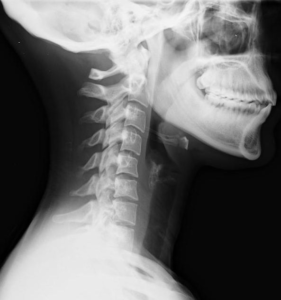

Después de un accidente de tráfico, ciertas lesiones son evidentes: huesos rotos, cortes, moretones. Pero, ¿qué pasa si el dolor persiste, pero no hay indicios visibles de lesión? El latigazo cervical, las conmociones cerebrales y las lesiones de tejidos blandos no siempre son evidentes en las radiografías o exploraciones, por lo que son más difíciles de comprobar. Las compañías de seguros son conscientes de esto y podrían utilizarlo como fundamento para reducir o rechazar su reclamación.

• Latigazo cervical: causado por el movimiento abrupto hacia adelante y hacia atrás del cuello, el latigazo cervical puede provocar dolor intenso, rigidez, dolores de cabeza y mareos.

Como no se puede señalar una radiografía y decir: “¡Mira, aquí está mi lesión!”, se deberá recurrir a otros tipos de pruebas para hacer entender el argumento. A continuación, se explica cómo:

Aunque las radiografías estándar no diagnostican lesiones de tejidos blandos ni lesiones en la cabeza, otros equipos sí lo hacen:

• Resonancia magnética (IRM): detecta lesiones en los tejidos blandos y en la cabeza.